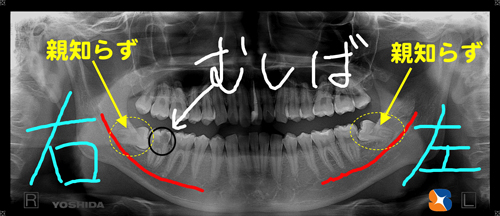

横向きの親知らず レントゲンの結果、右下には大きな虫歯(奥歯)と横向きの親知らずを確認。左下にも、横向きの親知らずを確認出来ました。